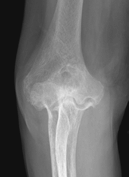

Figure 62-4 A: Stage III rheumatoid arthritis. B: Stage III rheumatoid arthritis.

Figure 62-5 A: Stage IV rheumatoid arthritis. B: Stage IV rheumatoid arthritis.